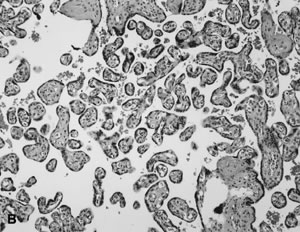

Partial hydatidiform mole, incorrectly referred to as a “transitional mole,” is the result of fertilization of a normal ovum by either two sperm (dispermic, diandrogenetic fertilization) or one diploid sperm (diandrogenetic fertilization).63 The tissue may be more abundant than expected for gestational age and usually includes membranes, rarely an umbilical cord or fetus. Only some villi are enlarged, resulting in a dual villous population (Fig. 4A and B). Variable syncytiotrophoblastic proliferation is the key to diagnosis. The diploid partial HM is reported to be more aggressive, yet some still question exactly what it may represent. Some clearly are complete HM, from early curettages in which the villous morphology has not completely developed, and others are twin gestations with a normal fetus and coexistent molar gestation.76,77 A diploid ovum may be fertilized by a normal haploid sperm (digynic fertilization), resulting in a triploid abortus without partial molar features (Fig. 4C).75 Choriocarcinoma is a rare complication of partial HM. The several case reports78,79,80 often fail to completely describe the preceding molar lesion.

Fig. 4. A. Triploid “partial” mole. Macrocystic vesicles interspersed with normal placental parenchyma. B. Partial hydatidiform mole with central cistern ( arrows ), irregular shape with stromal pseudoinclusions ( open arrow) and syncytiotrophoblast proliferation. (Hematoxylin-eosin, ×10.) C. Triploid non-molar placenta with two villous population, villous irregularity resulting in pseudoinclusions, and absent trophoblast proliferation. (Hematoxylin-eosin, ×10.)